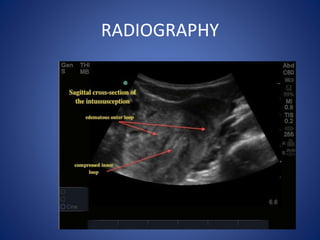

Ultrasound: small bowel

obstruction

RADIOGRAPHY